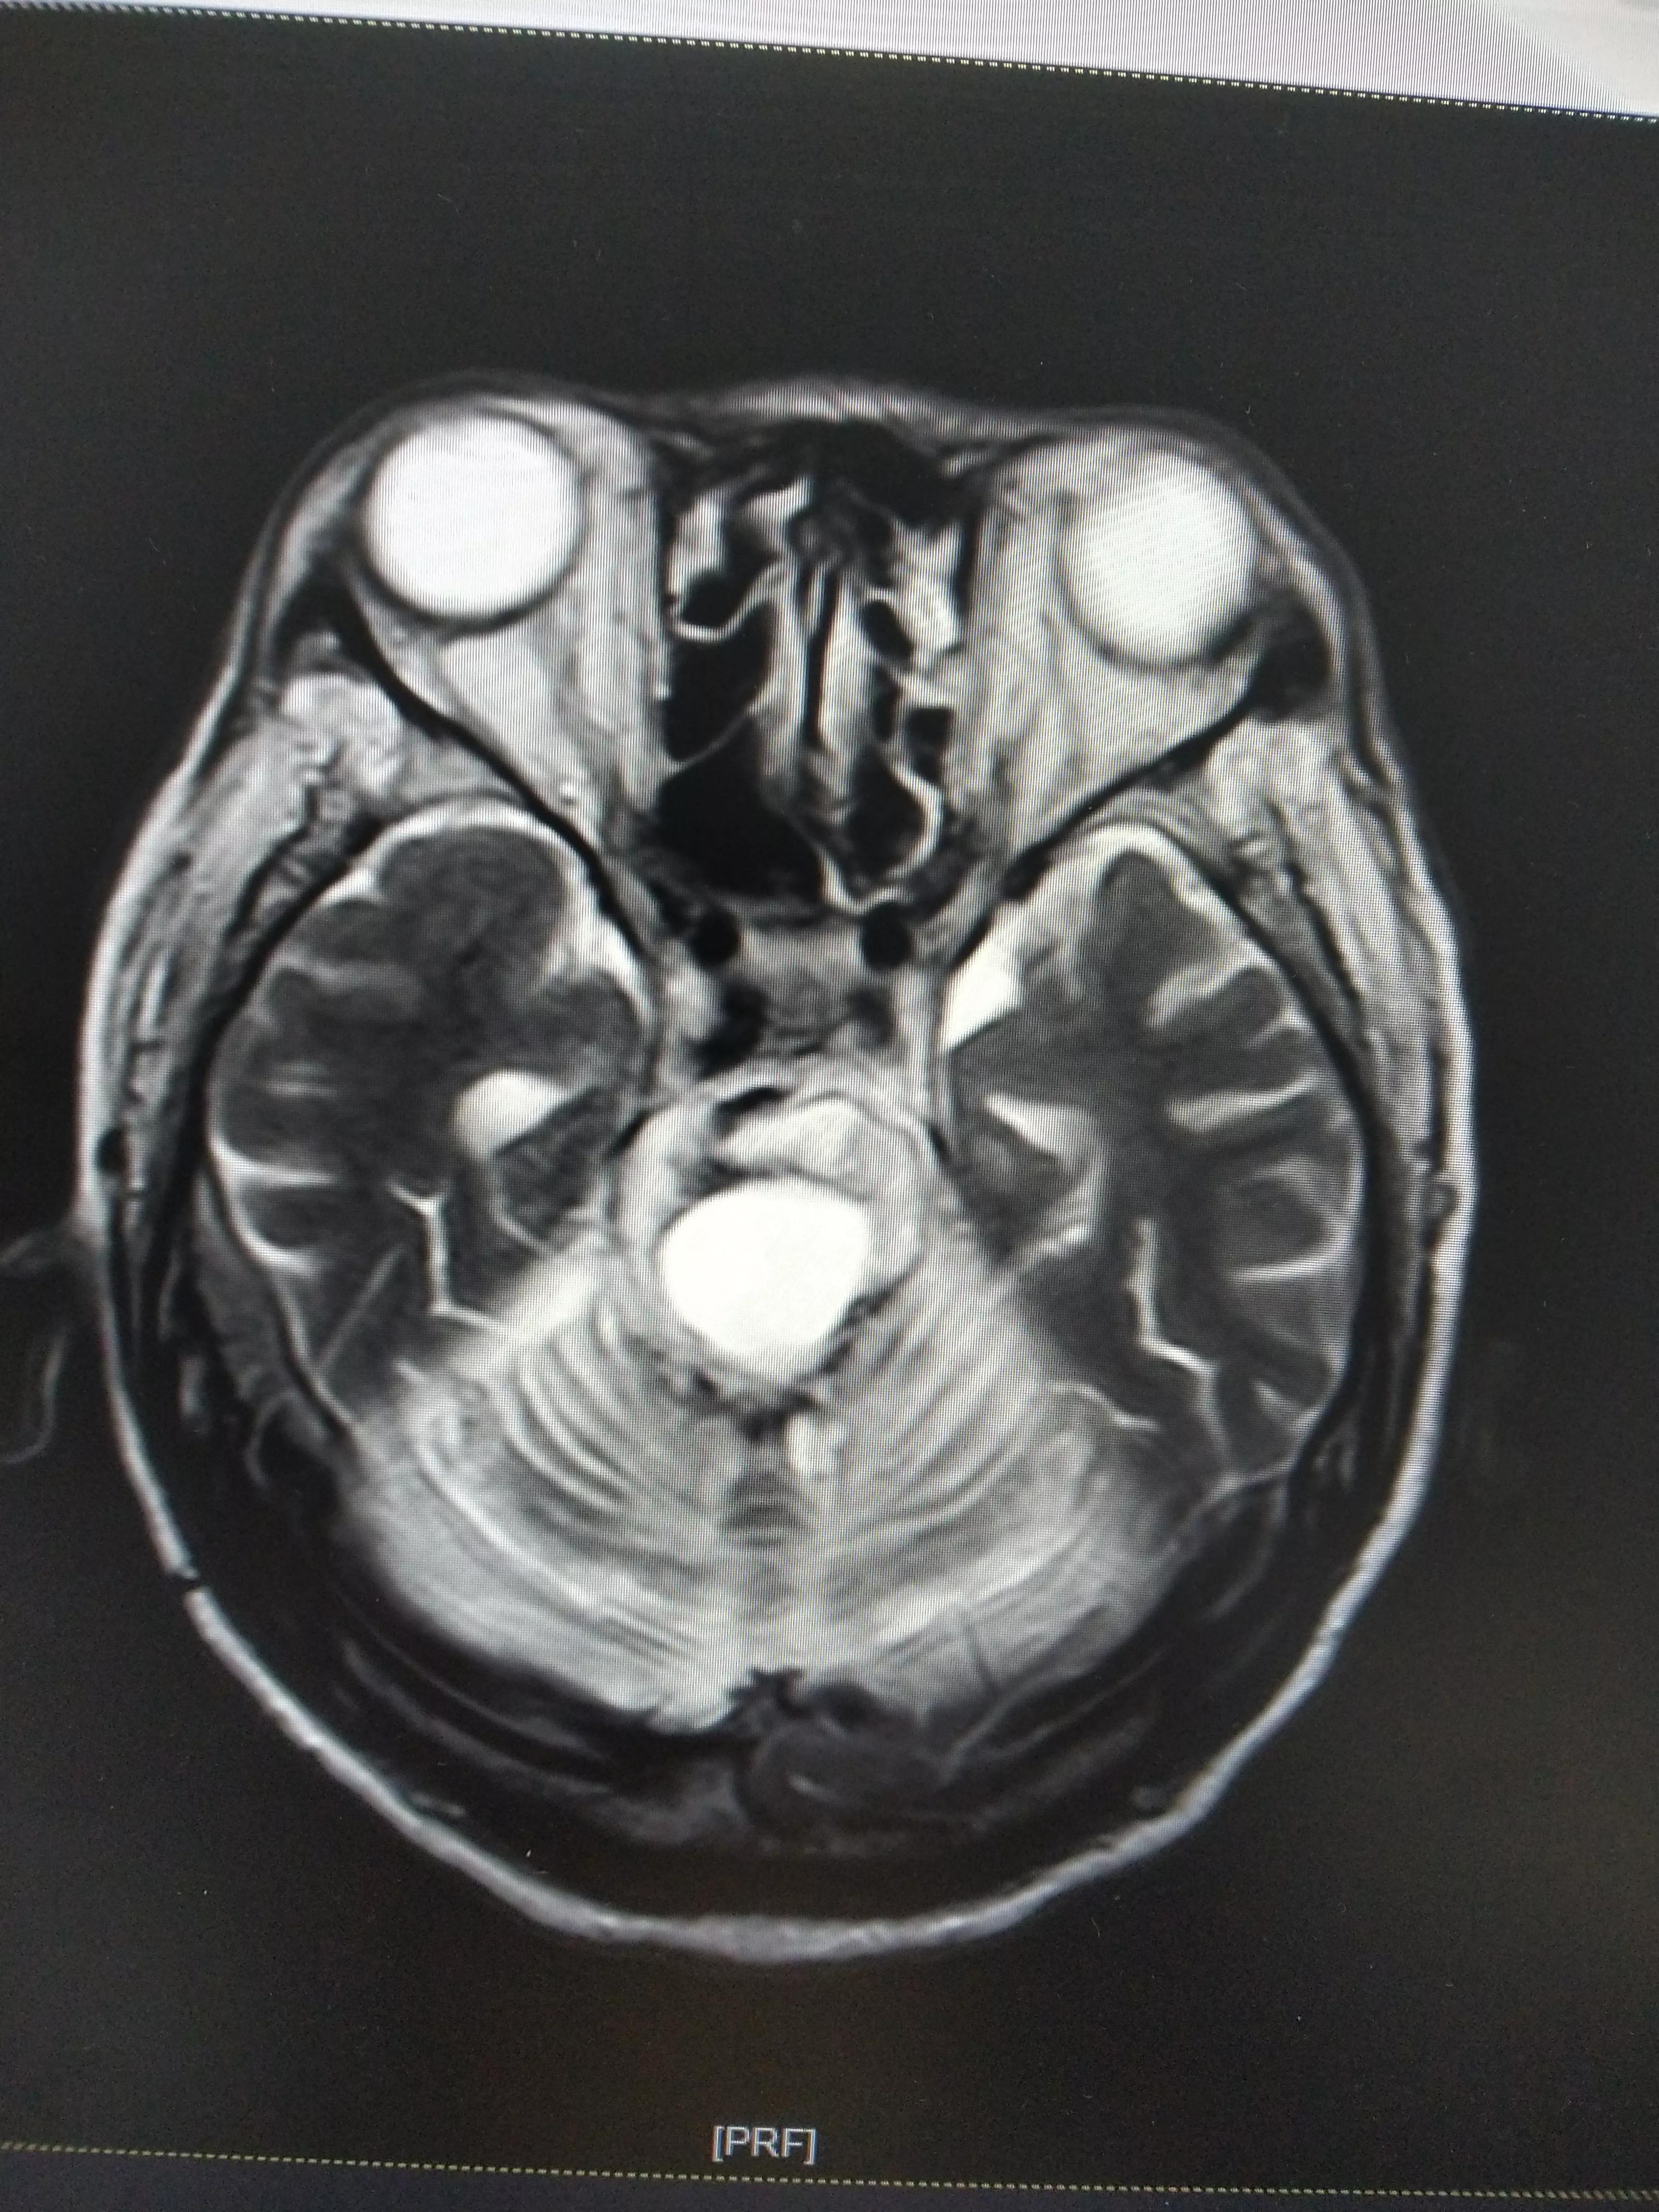

七,昏迷一年后复查颅脑核磁MR

1,脑干出血后,多发性软化灶2,双侧,额叶,顶叶基底节多发脑梗/腔隙性脑梗死。

3,双侧额叶,顶叶,基底节。异常信号考虑胶质增生可能。

4,脑积水。

5,脑萎缩脑白质病变(DWML1级,PVH1级)。